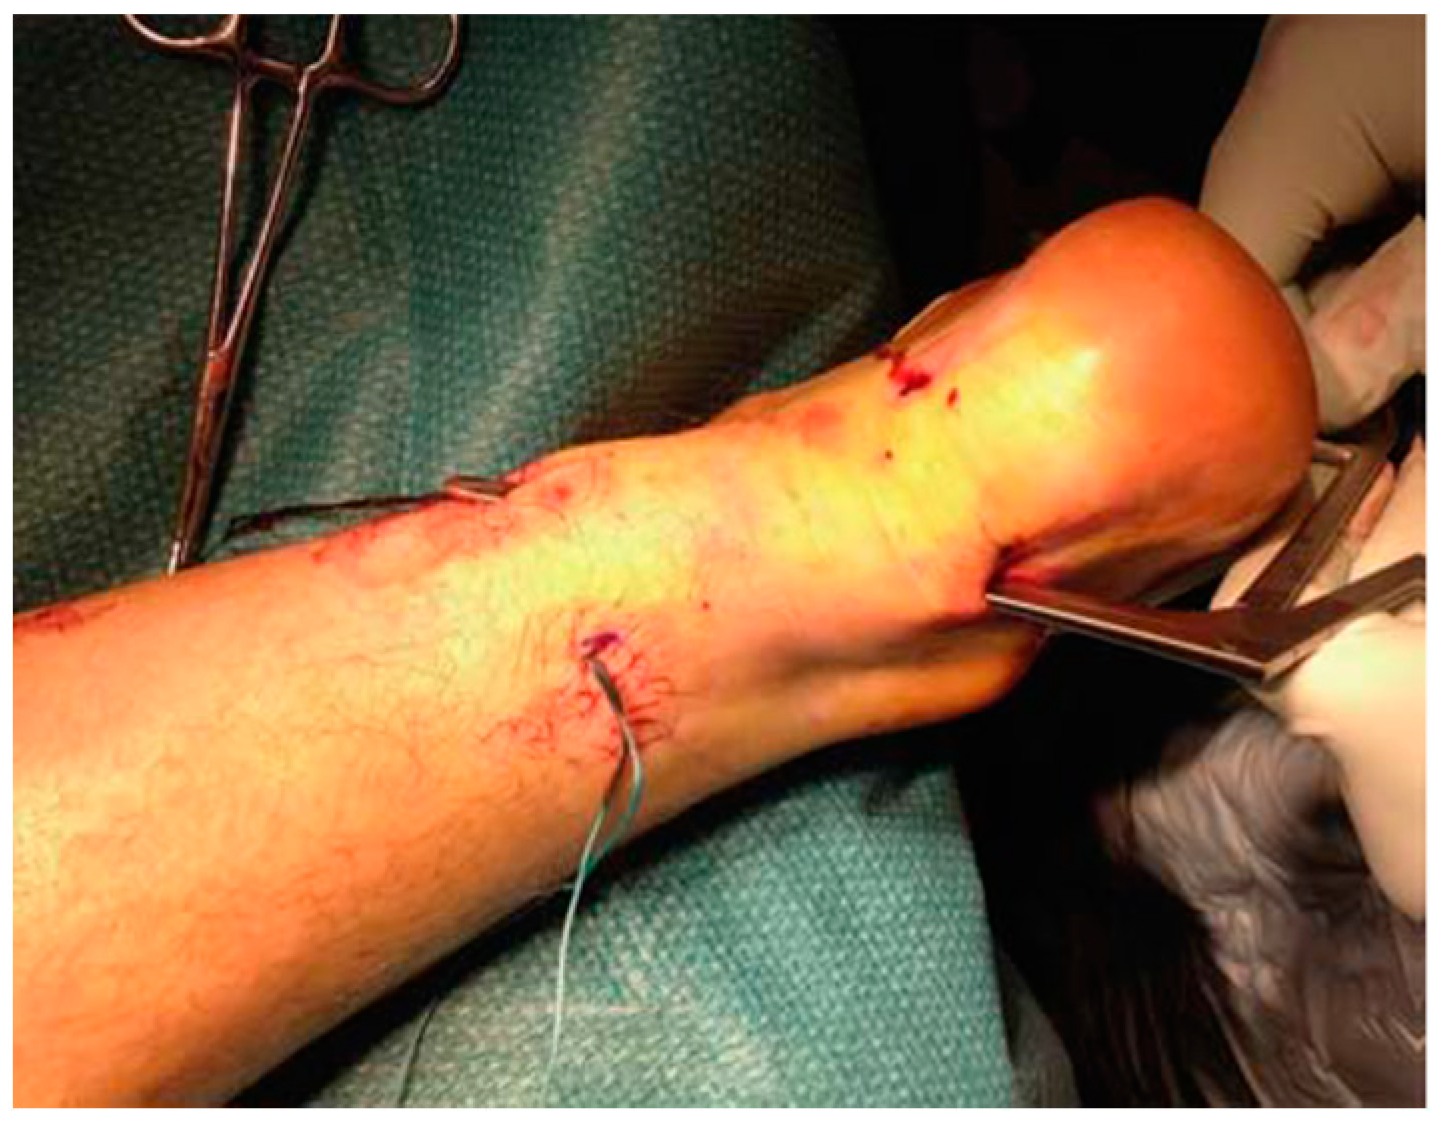

Longitudinal incisions are made from tendon medial size avoiding sural nerve and short saphenous vein injuries [18]. Tendinopathic tissue is identified and removed, and it appear with a disorganised fibre bundles with a “crabmeat” appearance [18]. Any gap can be repaired using a side-to-side repair and can remain unsutured, or if significant loss tissue occurs, a tendon augmentation or transfer can be considered. Peroneus brevis (Figure 7) or flexor hallux longus (Figure 8) tendons are the most frequently used local tendon grafts [43,125,126].

Figure 8.

Flexor hallucis longus tendon graft was harvested through a 2.5 to 3 cm longitudinal medial incision along the distal portion of the Achilles tendon.

Then, early rehabilitation with early motion is advocated, avoiding tendon overloading during the initial healing phase [18].